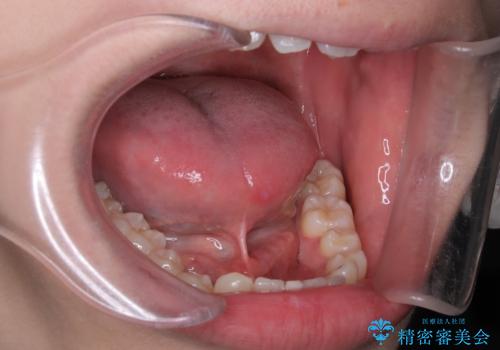

[ 舌小帯の形成術 ] ラ行の発音を改善したい

担当医 大元洋佑